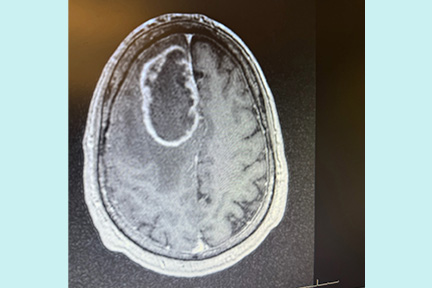

At Memorial Regional Hospital, imaging revealed the cause, a benign brain tumor. Scott describes that moment as surreal. He was confused, exhausted, and unsure what would come next.